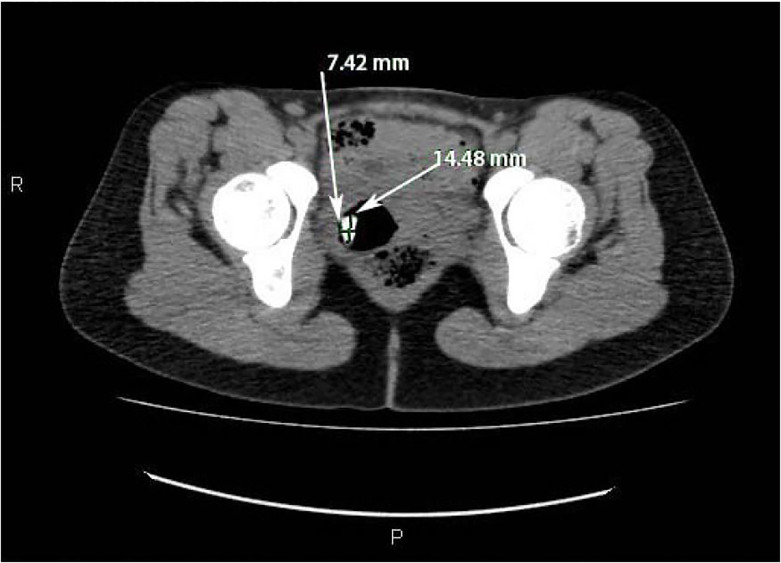

Figure 3. На аксиальной компьютерной томографии брюшной полости/таза стрелками обозначено рентгеноконтрастное образование в форме таблетки в шейке матки, которое распространяется в матку.